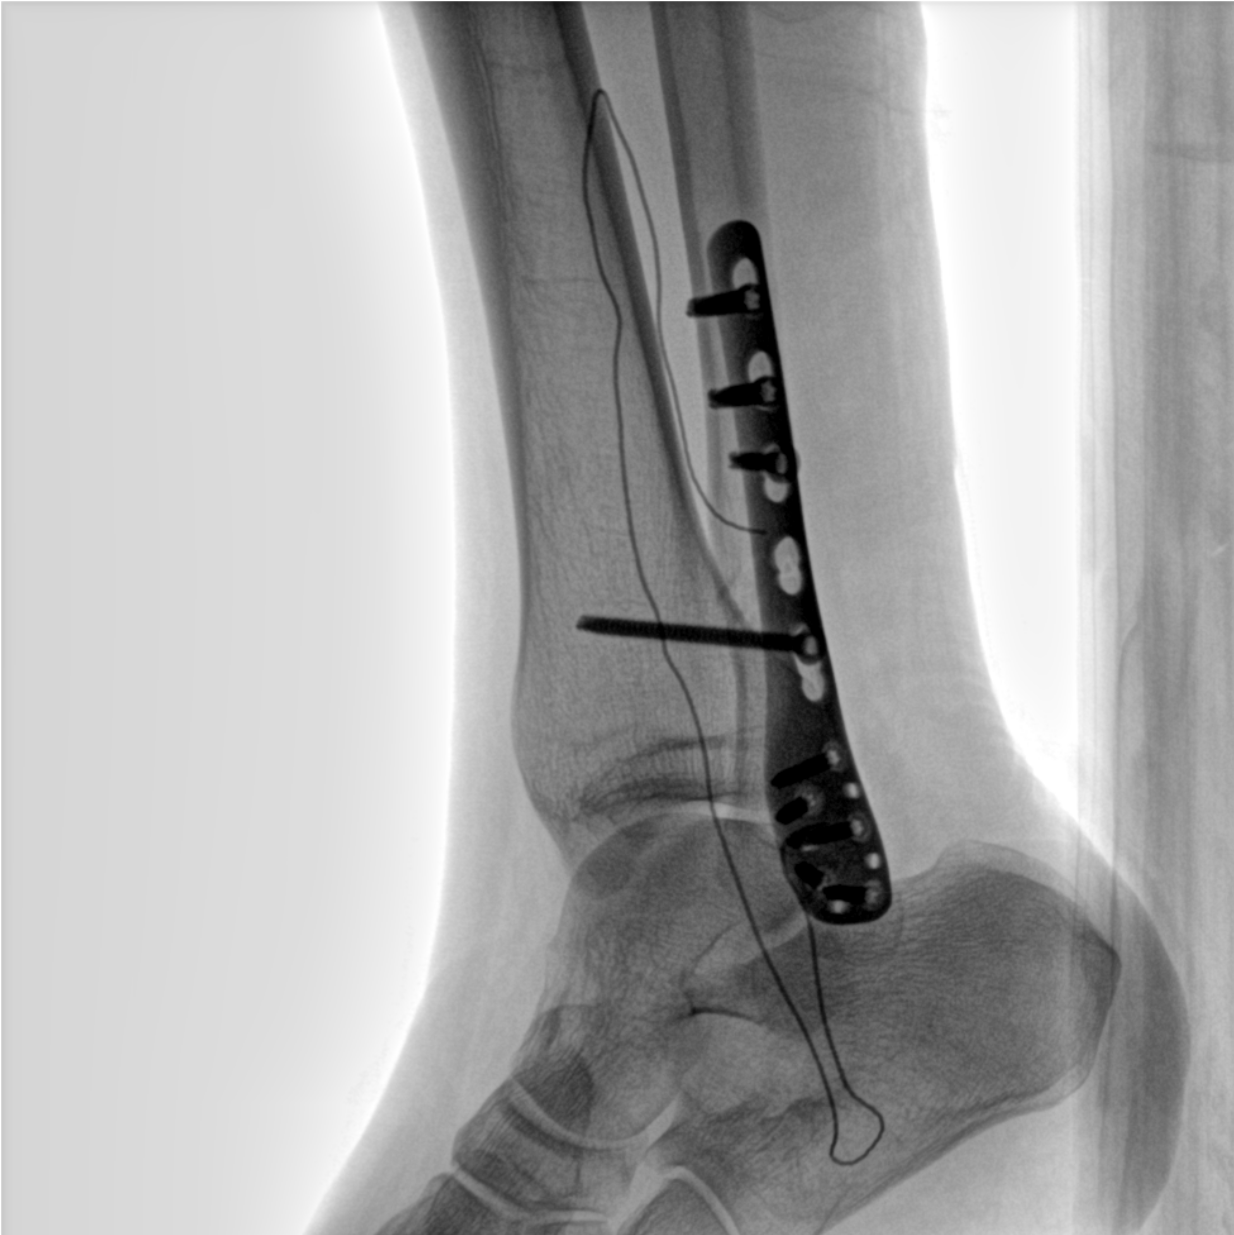

術(shù)中三維成像和橫斷面圖像提供多角度的手術(shù)診斷信息,輔助醫(yī)生進(jìn)行術(shù)中評(píng)估判斷,諸如骨折復(fù)位情況和內(nèi)植入螺釘?shù)某叽绾臀恢?,輔助手術(shù)更好地完成。

在C臂掃描過(guò)程中,始終保持拍攝主體處于射線束的中心,避免了序列圖像采集過(guò)程中的橫縱方向運(yùn)動(dòng),減少相對(duì)運(yùn)動(dòng)造成的運(yùn)動(dòng)偽影。

平板垂直升降運(yùn)動(dòng) 便于術(shù)中微調(diào)平板與拍攝主體的距離,更加貼近病灶體,成像范圍更大,圖像更清晰。